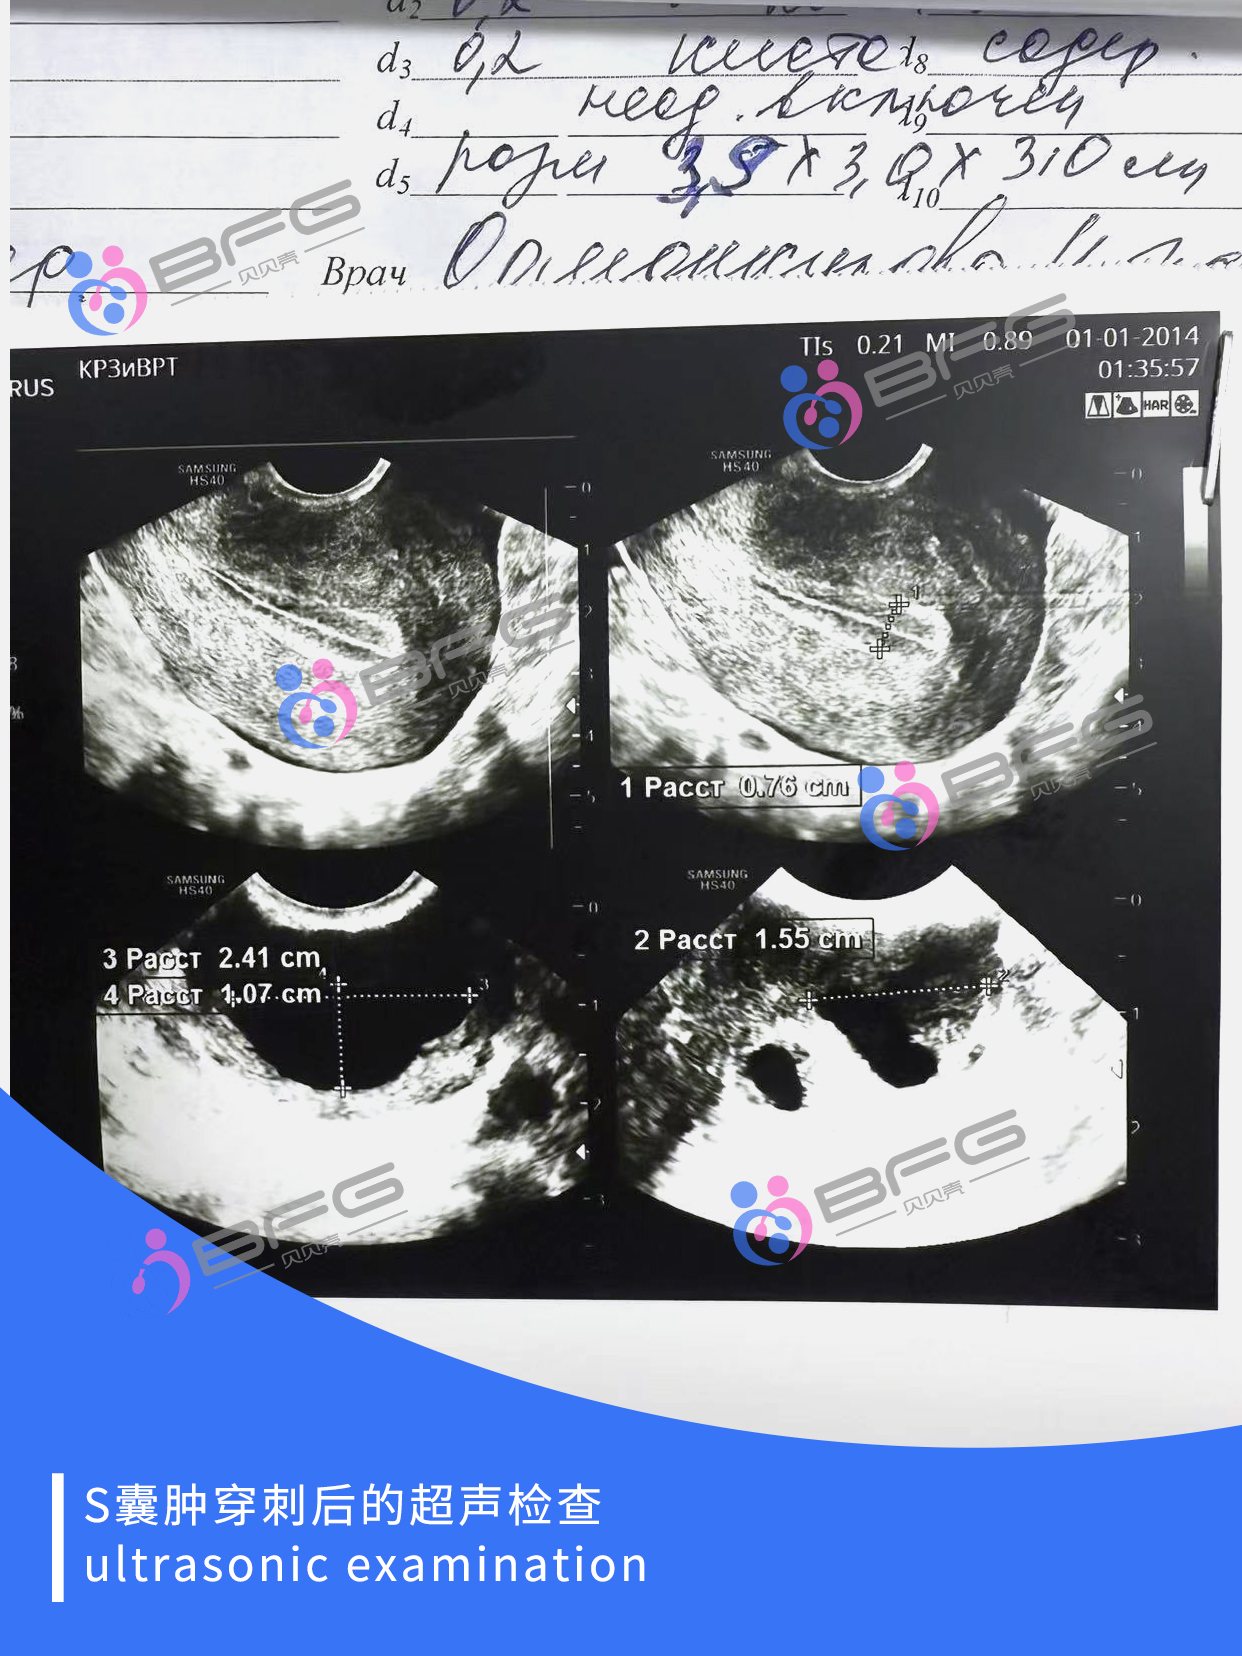

马上年底,一切都在有序进行中,期待这些好消息。

BFG以现代医学助力,帮助有孕育需求的家庭圆梦,让爱完整,让爱延续🍀